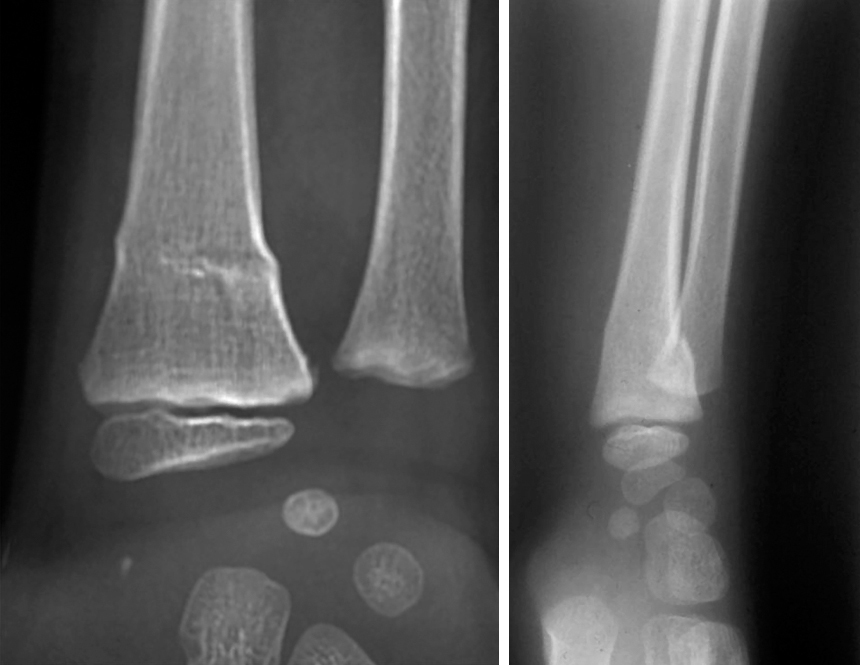

Quel est votre diagnostic ?

Il s'agit de l'aspect radiologique d'une fracture en motte de beurre chez l'enfant. Si certaines fractures sont proches de celles rencontrées chez l'adulte, d'autres sont en revanche spécifiques à l'enfant : fractures en motte de beurre, fractures en bois vert, déformation plastique, fractures sous-périostées, décollements épiphysaires. L'os de l'enfant est moins résistant que celui de l'adulte mais il n'y a pas de fracture sans traumatisme, donc pas de fracture avant l'âge de la marche. Le bilan radiographique comprend des clichés avec incidences de face et de profil, englobant les articulations sus- et sous-jacentes. Les clichés comparatifs ne sont pas nécessaires. Ces clichés sont réalisés après antalgie efficace (paracétamol et anti-inflammatoires non stéroïdiens). La fracture en motte de beurre, fréquente entre 3 et 8 ans, touche essentiellement le radius. Correspondant à un tassement métaphysaire par impaction de la diaphyse, cette fracture est stable, sans risque de déplacement secondaire. Son traitement est donc antalgique, soit par attelle amovible, soit par immobilisation plâtrée, durant 3 semaines. La radiographie de contrôle est inutile.